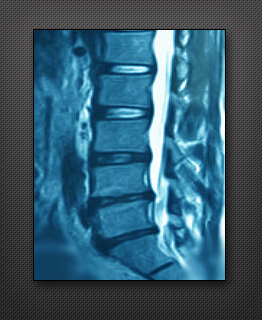

디스크 내장증

디스크 내장증은 디스크가 변성을 일으켜 요통을 유발하는 질환으로, 허리 디스크와는 엄연히 다른 질환입니다. 허리 디스크는 디스크가 척추 밖으로 튀어나와 신경을 누르지만, 디스크 내장증은 디스크 자체가 고장난 것입니다. MRI 검사상 정상 디스크는 하얗게 보이지만 내장증이 있는 디스크는 검게 보입니다. 디스크 내장증이 있어도 일부는 별다른 통증을 못 느끼지만 대부분은 요통을 호소합니다.

20~50대에 주로 발생하며 일상생활에 지장을 주는 정도의 만성 통증이 특징입니다.

특히 이 질환은 X선이나 CT상으로는 증상이 나타나지 않고 원인을 알 수 없어 여러 가지 치료방법을 전전하다 나중에야 정확한 병명을 알게되는 경우가 많습니다. 만성요통으로 8~12주 이상 보존적인 치료방법을 받았음에도 증상이 좋아지지 않는다면 디스크 내장증을 의심해 보아야 합니다.

디스크 내장증의 가장 큰 원인은 척추에 심한 충격을 받는 것입니다. 교통사고를 당하거나 무거운 물건을 오랫동안 들고 있으면 지지해 주는 디스크가 손상되면서 발병하게 됩니다. 주사, 약물요법, 물리치료 등으로 증상이 호전되지 않으면 수술적 치료를 고려 해야 합니다.